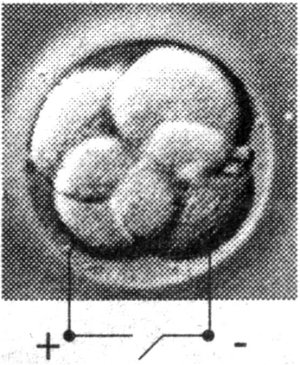

Aplica-se

uma descarga eléctrica para provocar a fusão do núcleo

transplantado com o ovócito. |